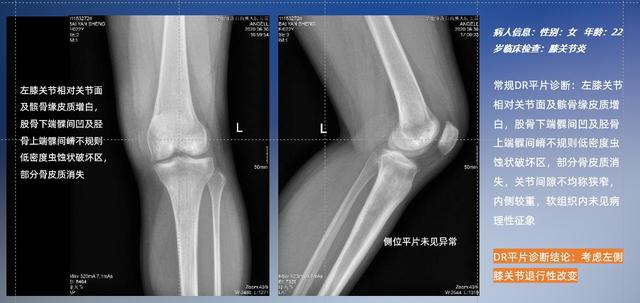

普通平片扫描与WR-3D扫描前后诊断结果对比

以膝关节疾病检查为例,膝关节在解剖学意义上是一种较为复杂的最大关节,由胫骨上端、股骨下端及髌骨组成。在股骨与胫骨的关节面之间存在两块半月板,分别处于内侧、外侧。膝关节的运动主要为伸、屈,在半屈位时可进行小幅度的旋外、旋内运动。随着现代人们体育生活以及肥胖的增加,膝关节疾病出现高发趋势,特别是关节磨损、膝关节炎与骨关节炎等关节退行性改变,长时间的内翻负荷会造成内侧关节软骨、骨性关节面的磨损。目前针对此类疾病的检查主要为平片下的负重位检查、CT检查以及MRI检查,相较于非负重位检查,负重位检查能更加真实反映膝关节结构中胫骨、股骨、髌骨实际对位关系和关节面的形态特征及关节间隙大小,对膝关节骨关节病诊断准确率高。

与此同时,数字化X线摄影技术相较于CTMRI来说,能快速获取真实、直观、满足临床需要的影像。DR的图像具有图像层次丰富、空间分辨力高、影像边缘锐利清晰、密度分辨力高级细微结构表现出色等特点,针对膝关节解剖结构数字化X线摄影技术应用价值很高,尤其是是对骨小梁与骨皮质的显示非常清楚。在负重位状态下,数字化X线三维摄影扫描与重建,能够更好的呈现受检者关节受力改变的状态。太阳成集团tyc122cc入口科技创新的WR-3D动态三维数字化X线摄影技术,通过数字化X线摄影完成三维扫描并重建三维影像信息,包括MPR多平面重建、MIP重建以及VR绘制。扫描时间短,剂量相较于CT设备大幅缩减,同时成本更低,在临床诊断以及医疗方案制定中具有极大的价值意义。相较于普通平片下的负重位扫描,负重位动态三维扫描摄影技术能够避免二维状态下的组织结构重叠、密度分辨率不足、组织解剖结构难以分辨等问题,WR-3D支持多角度的动态三维摄影观察,能全面的呈现被检查部位在多个角度下三维影像信息,极大的减少了二维负重位检查的漏诊率。